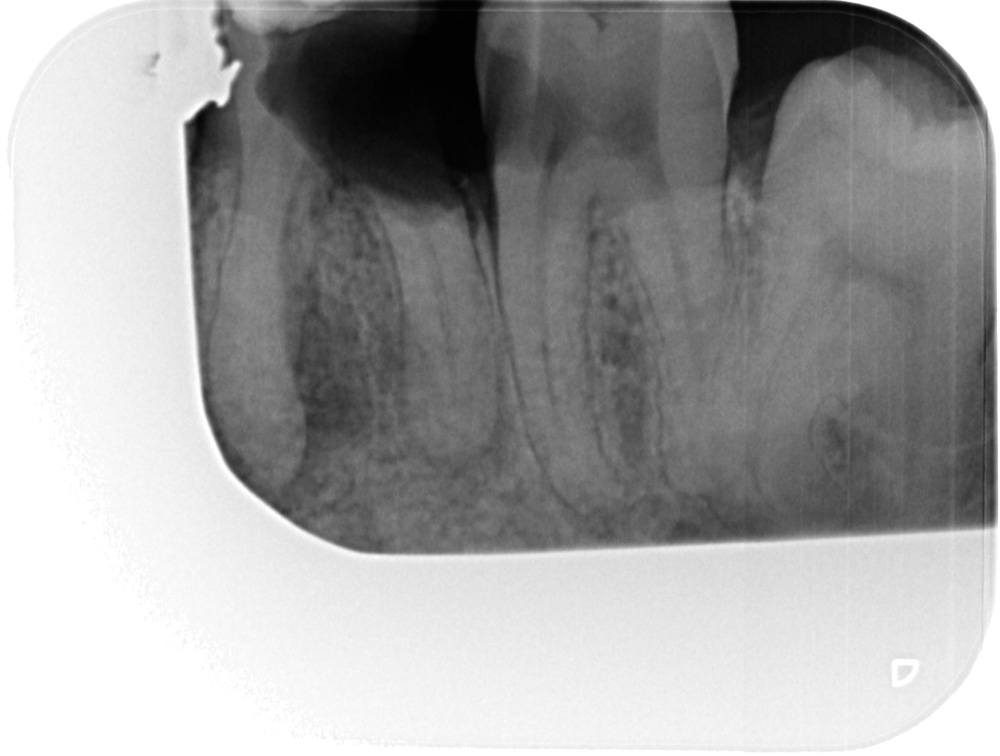

Ik voelde dat hij ook twee of drie boven tanden raakte . Dit is denk ik wel te zien daar het voor die doeleinde meer geen boor was , maar een frees was met een rond bolletje . De grote van de frees is ook goed te zien aan de tand erboven in mijn mond die hij beschadigd heeft .Ondnaks de verdoving voel je de triling van de boor Deze vulling is inmiddels er uit gevallen . Wat later werd de eerste foto gemaakt

Na enkele minuten werd er pas een tweede foto gemaakt omdat zoals de Bali assistente zei er stond op de eerste foto maar een tand.op

Toen hij klaar was zei hij dat het op de eerste foto nog kon ""kaakoverzicht foto"", Maar zoals hij zei op de foto die genomen is 21-10-2021 niet , dat snap ik ook wel de kies was net door hem weggefreest

Er is geen nieuwe foto tenminste geen begin foto gemaakt Element 36 is niet meer te behouden Deze foto is pas gemaakt nadat hij element 36 had weg gefreest en 37 was al geopend voor een wortel kanaal behandeling

Er zijn op de fotos ookop element 36 en 37 geen wortepunt onstekingen te zien

Toen ik zei dat het volgens mijn twee second opinions het de gewoonte was om detail foto te maken . Daarop zei de weledelgeleerde tandarts A Padrao dat hij dat ook had gedaan .Waarop ik zei dat hij dat had gedaan nadat de kies element 36 was weggefreest!!. Ook bij een second opinion zeg de betreffende tandarts:Hij kon er niets over zeggen er was geen beginsituatie . Daar waar het vraagteken staat er is geen beginfoto .